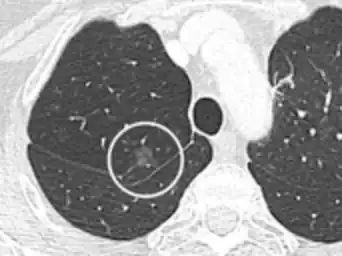

There are numerous potential causes of nodular GGOs which can be broadly separated into benign and malignant conditions. Benign conditions potentially leading to the formation of nodular GGOs include aspergillosis, acute eosinophilic pneumonia, focal interstitial fibrosis, granulomatosis with polyangiitis, IgA vasculitis, organizing pneumonia, pulmonary contusion, pulmonary cryptococcus, and thoracic endometriosis. Focal interstitial fibrosis presents a unique challenge when differentiating from malignant nodular GGOs on CT imaging. It is typically persistent over long-term imaging follow-up and shares a similar appearance to malignant nodular GGOs.[9]

Pre-malignant or malignant causes of nodular GGOs include adenocarcinoma, adenocarcinoma in situ, and atypical adenomatous hyperplasia (AAH). One large review study found that 80% of nodular GGOs which were present on repeated CT imaging represented either pre-malignant or malignant growths. Differentiating between pre-malignancy and malignancy on the basis of CT alone can pose a challenge to radiologists; however, there are several features that are indicative of pre-malignant nodules. AAH is a pre-malignant cause of nodular GGO and is more commonly associated with lower attenuation on CT and smaller nodule size (<10 mm) compared to adenocarcinoma.[10] In addition, AAH often lacks the solid features and spiculated appearance that are often associated with malignant growths.[9] In contrast, as adenocarcinoma becomes invasive it will more often cause retraction of adjacent pleura and may show an increase in vascular markings. Nodules >15 mm almost always represent an invasive adenocarcinoma.[9][10]